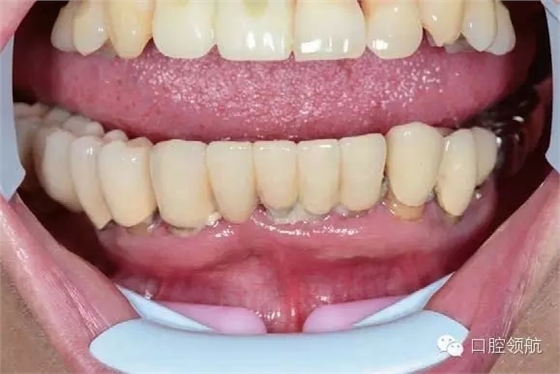

手術(shù)當天取模,當天灌注石膏模型,上牙合架,開始準備制作螺絲固定的過渡義齒(圖6-11,圖6-12)。

圖6-13和圖6-14分別為牙合架上的塑料過渡義齒。因為考慮縮短制作的時間,因此All-o n-4的術(shù)后螺絲固位過渡義齒使用自凝材料,同時用硅橡膠包埋蠟牙法制作。

同時因為是即刻負重,為了減少不必要的風(fēng)險,通常不制作遠中的游離端,該病例即刻負重過渡義齒修復(fù)到兩側(cè)的第二前磨牙,待永久修復(fù)時再增加兩側(cè)的第一磨牙。